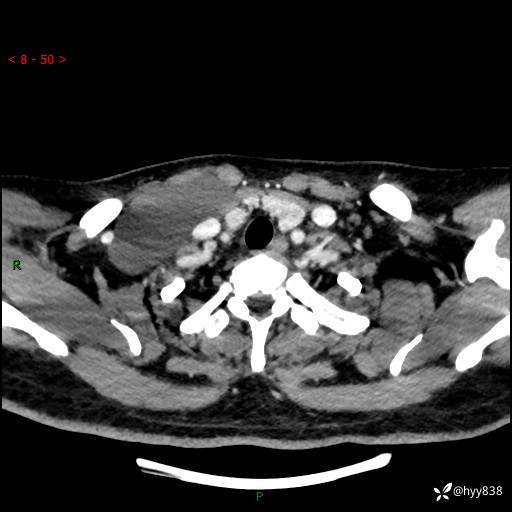

颈部CT平扫